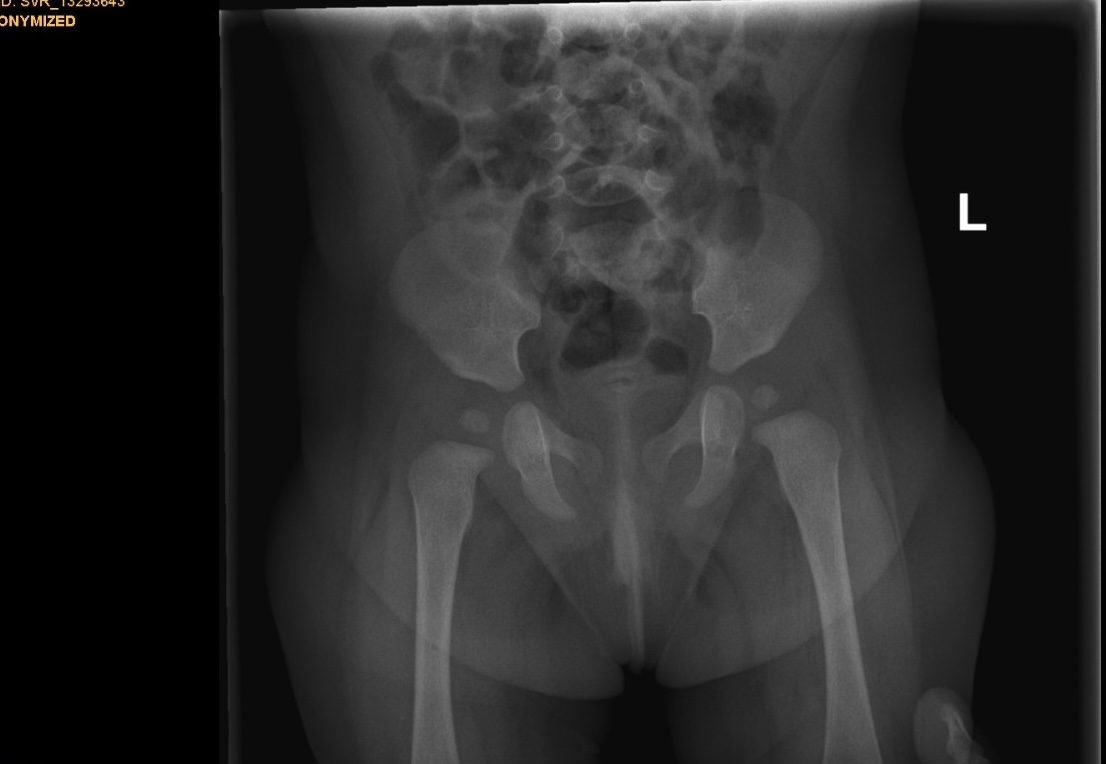

Дисплазия сустава у младенца

Дисплазия сустава у младенца 114 фотографий